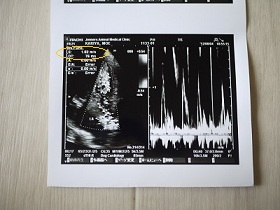

先生が、いつも心臓を評価する時に撮る波計。

今日はE波が1.52m/sもありました(´Д`汗)

通常なら肺水腫を疑う数値ですが、大興奮なのでアテにならない^^;って。

心音を、じっくり聞いて肺の音はクリア。でも心臓への負担はある。との判断でした。